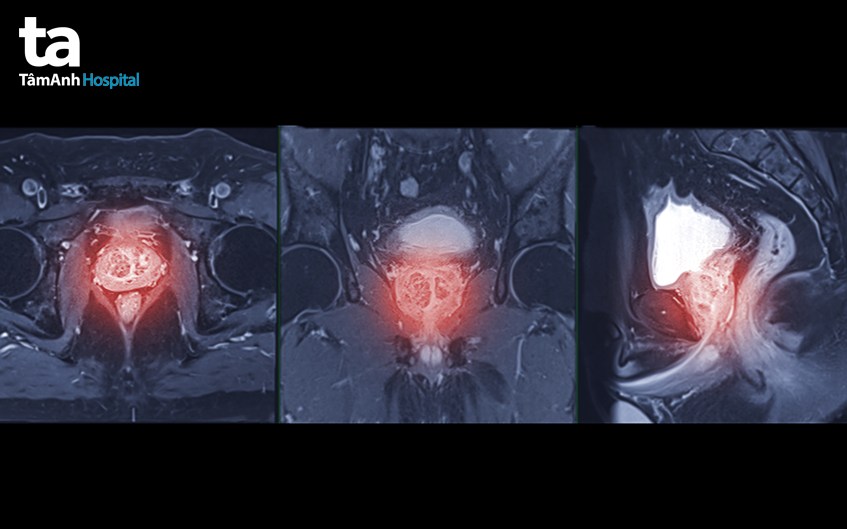

Tuyến tiền liệt là một tuyến nhỏ nằm bên dưới bàng quang và phía trước trực tràng. Bộ phận thuộc hệ tiết niệu này chỉ có ở nam giới. Một tuyến tiền liệt khỏe mạnh sẽ có kích thước bằng hạt dẻ và trọng lượng dao động từ 20-30 gram. Chức năng chính của tuyến tiền liệt là sản xuất chất lỏng, được gọi là dịch tuyến tiền liệt, chiếm 70% bên trong tinh dịch.

Tuyến tiền liệt được bao bọc bởi các mô liên kết gồm nhiều sợi cơ trơn và mô liên kết đàn hồi. Các tế bào cơ trơn cũng xuất hiện ở bên trong tuyến tiền liệt, có cơ chế co lại và ép mạnh dịch tuyến tiền liệt đến niệu đạo trong quá trình xuất tinh.

Tuyến tiền liệt được chia thành 3 vùng chính: (2)